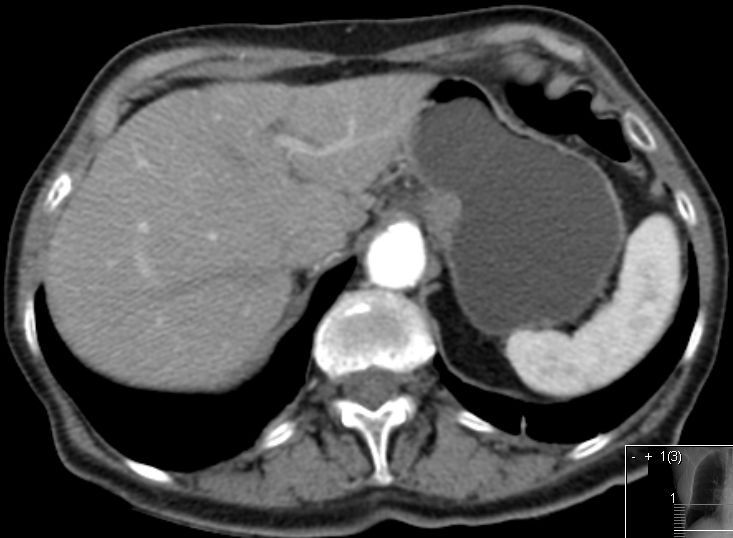

Magen 62-jährige Frau mit kolikartigen Flankenschmerzen durch einen mittlerer Harnleiterstein. Bei der Durchuntersuchung fand sich eine verdickte Magenwand. Endoskopisch chronische, nicht aktive Entzündung mit foveolärer Hyperplasie. Die Biopsie ergab Infiltrate eines gering differenzierten neuroendokrinen Karzinoms (G3, Ki 67 40%). Bekannte Haemangiome der Leber.